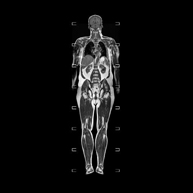

Prova diagnòstica no invasiva que consisteix en l'obtenció d'imatges d'alta definició anatòmica de la glàndula prostàtica mitjançant l'ús d'un camp electromagnètic i ones de ràdio (amb un emissor i un receptor). No utilitza radiació ionitzant. S'utilitza una bobina endorectal per obtenir imatges de màxima definició anatòmica de la pròstata i permetre fer l'estudi espectroscòpic (estudi a nivell molecular que ajuda a diferenciar les cèl·lules d'origen maligne o tumoral). També es realitza l'estudi amb contrast paramagnètic, que aporta una millor definició tissular. Aquesta prova dura uns 40 minuts, durant els quals el pacient haurà d'estar el més quiet possible. Requereix una neteja del còlon com a preparació prèvia. Aquesta prova està especialment indicada en aquells pacients amb sospita de neoplàsia de pròstata, amb neoplàsia de pròstata coneguda per l'estadiatge tumoral, per a l'estudi de localització del tumor prostàtic com a guia o mapa per a la biòpsia, per al seguiment dels pacients amb neoplàsia de pròstata tractats amb tractament quirúrgic o radioteràpic, davant d'una sospita de reincidència de la neoplàsia de pròstata, etc. - RM de Cos sencer (Total body)

Prova diagnòstica no invasiva que consisteix en l'obtenció d'imatges d'alta definició anatòmica de tot el cos mitjançant l'ús d'un camp electromagnètic i ones de ràdio (amb un emissor i un receptor). No utilitza radiació ionitzant. És una prova molt important en la recerca de metàstasi en pacients amb neoplàsia coneguda. No requereix preparació prèvia. No és necessari l'ús de contrast paramagnètic (Gadolini). - Angio-RM d'Aorta abdominal